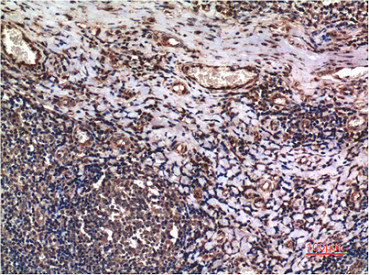

Immunohistochemical analysis of paraffin-embedded Human lung Tissue using Cyclin B1 Mouse mAb diluted at 1:200.

Immunohistochemical analysis of paraffin-embedded Human Tonsil Tissue using Cyclin B1 Mouse mAb diluted at 1:200.